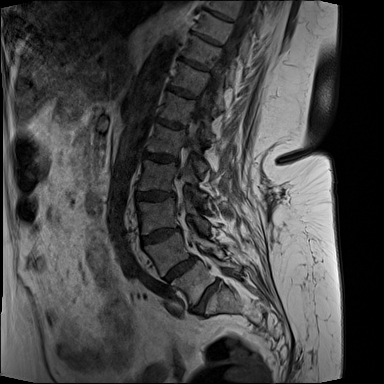

MRT Lendenwirbelsäule + Röntgen Becken - Diagnostik vor OP-Planung

19.01.2024

MRT Lendenwirbelsäule (LWS)

71 Bilder | 1024x1024 px | 15 MB

Januar 2024

MRT LWS + Röntgen Becken

MRT der Lendenwirbelsäule und Röntgen des Beckens zur Diagnostik

MRT LWS (Lendenwirbelsäule)

DICOM

MRT mit 71 Bildern